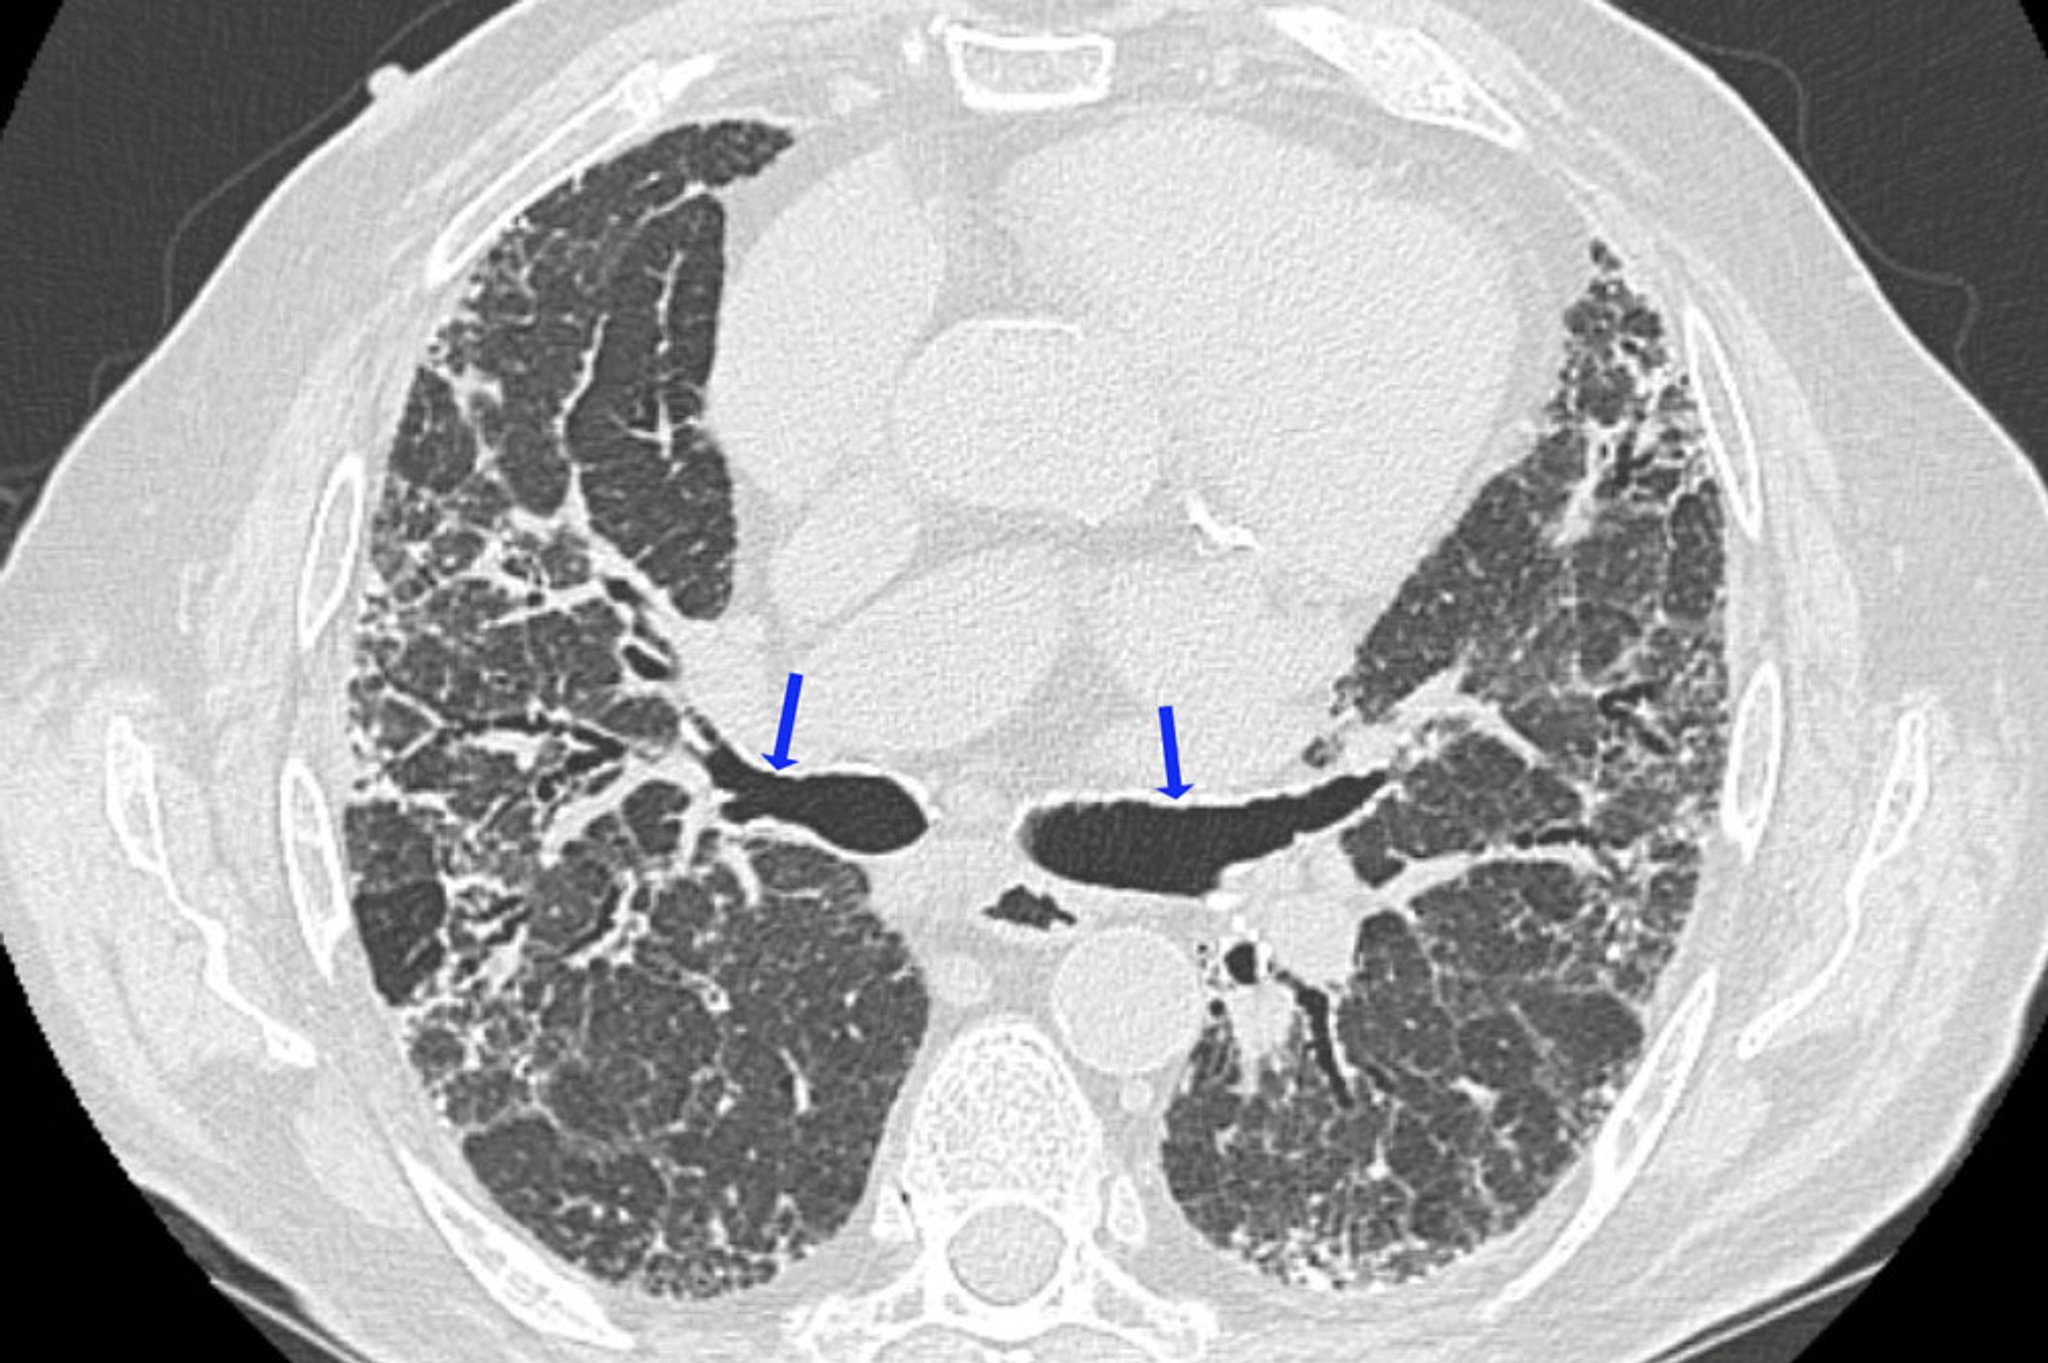

Pneumopathie d'hypersensibilité chronique

Cette TDM à haute résolution montre des signes de fibrose, dont une réticulation irrégulière et une bronchectasie de traction (flèches). Les zones de diminution de la densité pulmonaire sont compatibles avec les régions d'obstruction des voies respiratoires. Cette association de signes évoque une pneumopathie d'hypersensibilité.

Image courtoisie de Joyce Lee, MD, MAS.